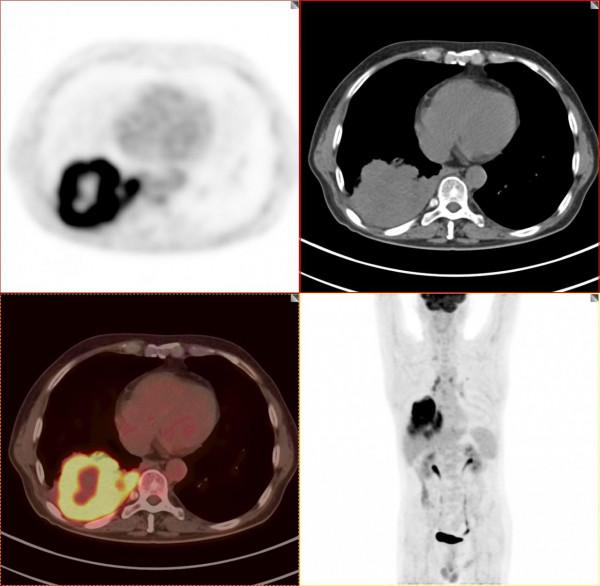

依據影像學分期,該患者後續進行了綜合治療:免疫+化療+靶向治療,其中化療3期,免疫治療2期及靶向治療。3個月後患者再次進行了PET/CT檢查,對治療效果進行了評估。2021年11月PET/CT檢查結果:

腫瘤病灶明顯縮小、實性成分明顯減少,腫瘤FDG代謝明顯減低,相鄰胸膜浸潤明顯改善,已經沒有胸水徵象。另外,全身其他部位未見明確轉移性病變。

複查後PET/CT診斷:右肺下肺癌綜合治療後,腫瘤病灶明顯縮小,FDG代謝明顯減低,相鄰胸膜未見高代謝病變,考慮腫瘤治療後療效顯著,僅少量腫瘤活性殘留。

根據我們PET/CT診斷,患者第二天就進行殘餘右肺癌病灶的手術切除。透過上述綜合治療,將一個原本沒有手術機會的患者從死神的手中搶回來。雖然愈後情況有待進一步觀察,但是透過PET/CT評價,患者病情明顯好轉,身體素質明顯好轉,生活質量明顯提高,將不可能變為可能。後續進一步療效,我會密切關注,後期隨訪再和大家分享。